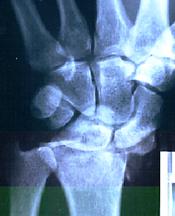

Some time ago I did a Tae Kwon Do Training with my young son. Running down the hall I slipped, fell into the wall and broke my wrist in about 50 places. Shattered the bone!

The surgeons told me the wrist could not be repaired because when the bone was shattered the circulation would not return to the bone, the coating on it would die and the raw bone on bone caused major pain. They said they would have just locked the bones together but with several centimeters of bone missing there was nothing to lock the hand onto.

They cut the wrist open, picked out the bits of bone, fitted the big pieces back, with 4 pins to stabilize them, and used the little bits of bone to fill up the cracks in the hope of grafting the bone.

The cast came off at 6 weeks. Despite the insistence by the surgeons that there was no chance of circulation returning to the bone the x-rays showed that all points of break healed with no problem areas.

Lots of people praying and massive use of Herbalife products seemed to do the trick. The surgeons removed the pins and there have been no problems since.